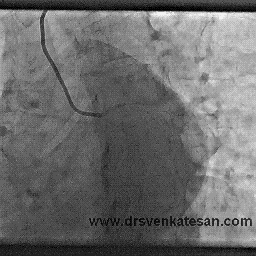

Here is  the  angiogram  which shows classical intra coronary bridging  collaterals.

Lessons  from  a unique patient we have  encountered.

Here is an example of total LAD/LCX  occlusion with good collateral  from  RCA. He was having  stable  angina on medical  management . This patient  was not only  asymptomatic and was also negative for exercise  stress test at moderate work load .

There was an  intense debate about the management  when this angiogram was presented in the cath meeting .

• Most of the cardiologists believed so !  But they had no answers why his stress test was negative.

• The other argument for CABG was one can not allow a patient with a functionally single coronary  artery (RCA) However good is the collateral circulation.This at least  has some logic. not the first one !

He  ultimately went on to receive CABG (By popular opinion ) , but the point here is the collaterals were  good enough to support exertion.We have  documented quiet a few similar patients with collateral circulation supporting exercise.